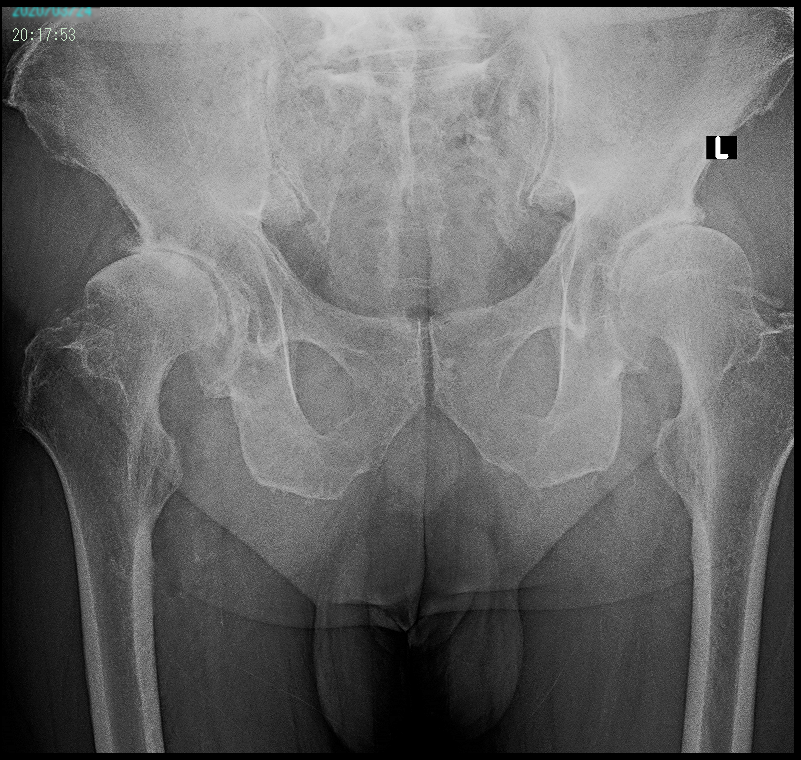

下図は52才の女性で介護職の方です。X年12月13日に当院を受診されました。初診時、身長162㎝、体重92㎏でかなり肥満傾向の強い方でした。

岡崎例 1.jpg

左は重度の変形性股関節症で、右も中等度の変形性股関節症です。

初診時に当院の人工関節手術のパンフレットを渡して、左股関節の根本的な治療は手術しかないと説明していますが、患者さんは、手術はしないと強い決意を述べられました。